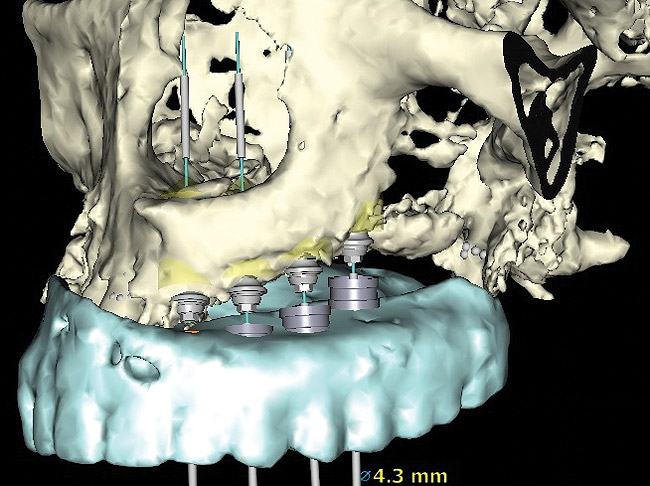

Figure 14  Virtual treatment plan, patient in Figure 12 and Figure 13.

Figure 14

Figure 15  Surgical guide in place. Implants attached to implant mounts and placed to depth.

Figure 15

Figure 16  Laboratory-processed provisional restoration fabricated prior to surgery.

Figure 16

Figure 17  Provisional restoration placed at time of surgery.

Figure 17